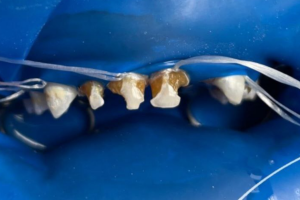

Семейная областная стоматология "Кидди Дентал" - это команда компетентных врачей, каждый из которых знает и любит свое дело. Опыт наших врачей, использование современного оборудования и надежных материалов позволят проводить лечение любой сложности.